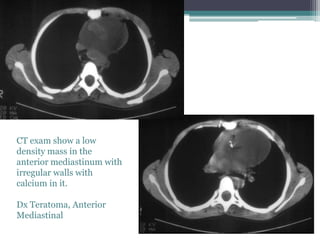

Eight year old male with a

heart murmur

โ–ซ PA and lateral chest films show a

large anterior mediastinal mass

causing narrowing and rightward

deviation of the trachea. The

mass is not calcified.

CT exam show a low

density mass in the

anterior mediastinum with

irregular walls with

calcium in it.

Dx Teratoma, Anterior

Mediastinal